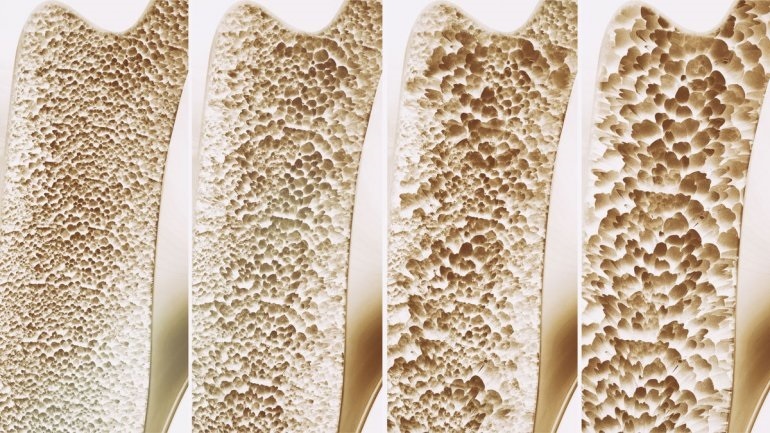

Ο περιορισμός βάδισης αυξάνει τον κίνδυνο κατάγματος

Ο περιορισμός στο περπάτημα σχετίζεται σημαντικά με τον κίνδυνο κατάγματος σε μια διάρκεια 4-5 ετών, σύμφωνα με μια μελέτη που δημοσιεύθηκε στο JAMA Network Open.